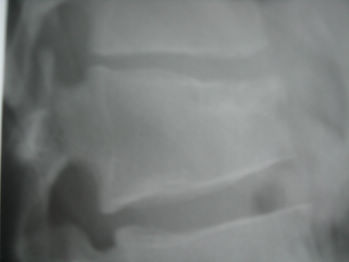

要鉴别就要分清楚死骨、瘤骨/成骨及钙化。该l1/2椎间盘狭窄是由于压缩性骨折而胸腰段曲度后突畸形所致,头二副轴位图像看不到明显骨质破坏,更不要说tb感染椎间盘了。且骨质破坏区太过干净,囊状低密度区边界清晰又有硬化,最重要软组织无改变,病史长达2年无tb症状,不支持感染性/tb病变。

考虑可能性骨母合并abc>骨血管瘤>tb>软骨母。

不像tb,周围没有冷脓肿,这个边缘好像有硬化,

不是结核,陈旧性压缩骨折,椎体前缘软骨结节

不支持结核,压缩性骨折并舒-帽氏结节,骨母细胞瘤常见于附件。

骨质破坏区太过干净,囊状低密度区边界清晰又有硬化,最重要软组织无改变,病史长达2年无tb症状,不支持感染性/tb病变。

考虑椎体前缘软骨结节